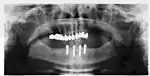

Biomechanical considerations

The long-term success of implants is determined in part by the forces they have to support. As implants have no periodontal ligament, there is no sensation of pressure when biting so the forces created are higher. To offset this, the location of implants must distribute forces evenly across the prosthetics they support.[29]: 15–39 Concentrated forces can result in fracture of the bridgework, implant components, or loss of bone adjacent the implant.[30] The ultimate location of implants is based on both biologic (bone type, vital structures, health) and mechanical factors. Implants placed in thicker, stronger bone like that found in the front part of the bottom jaw have lower failure rates than implants placed in lower density bone, such as the back part of the upper jaw. People who grind their teeth also increase the force on implants and increase the likelihood of failures.[16]: 201–208

When a more exacting plan is needed beyond clinical judgment, the dentist will make an acrylic guide (called a stent) prior to surgery which guides optimal positioning of the implant. Increasingly, dentists opt to get a CT scan of the jaws and any existing dentures, then plan the surgery on CAD/CAM software. The stent can then be made using stereolithography following computerized planning of a case from the CT scan. The use of CT scanning in complex cases also helps the surgeon identify and avoid vital structures such as the inferior alveolar nerve and the sinus.[32][33]: 1199

During surgery

Placement of dental implants is a surgical procedure and carries the normal risks of surgery including infection, excessive bleeding and necrosis of the flap of tissue around the implant. Nearby anatomic structures, such as the inferior alveolar nerve, the maxillary sinus and blood vessels, can also be injured when the osteotomy is created or the implant placed.[68] Even when the lining of the maxillary sinus is perforated by an implant, long term sinusitis is rare.[69] An inability to place the implant in bone to provide stability of the implant (referred to as primary stability of the implant) increases the risk of failure to osseointegration.[29]: 68